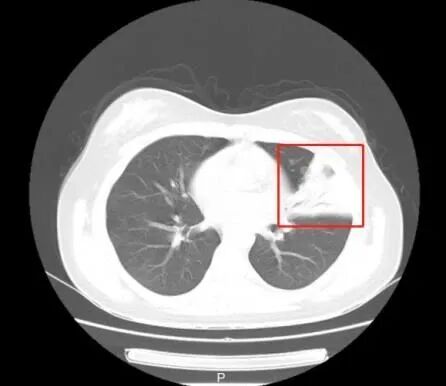

这下,安安的家长急坏了,带着孩子来到浙江省立同德医院儿科就诊,拍了胸部CT显示,左侧肺炎(见下图),正常应该显示黑色为主的部分都白了,实变得很厉害,儿科医生看过CT后,立即给孩子安排了住院治疗,入院以后完善相关病原检测,发现肺炎支原体检测阳性,导致肺炎的“元凶”很可能就是它。